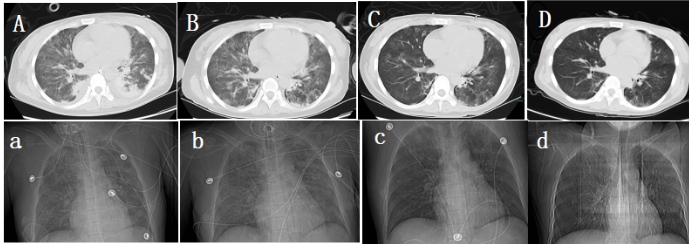

1.3.2 影像学检查2021-04-14彩色多普勒超声:右侧甲状腺下极下方低回声,大小2.3 cm×1.5 cm,边界清,甲状旁腺来源首先考虑(图 1A, B);双肾B超提示:双肾肿大伴肾病表现。2021-04-17颈部CT:右侧甲状腺后方结节(图 1C)。心脏超声:主瓣瓣环及二尖瓣瓣环及二尖瓣腱索上多发钙化,左室壁偏厚,肺动脉压增高。肺部CT:两肺炎症病变,两侧少量胸腔积液(图 2A)。

| A、B:多普勒超声示右侧甲状腺下极下方2.3 cm× 1.5 cm低回声;C:颈部CT示右侧甲状腺后方结节(箭头所指部分) 图 1 甲状旁腺术前影像学定位检查 |